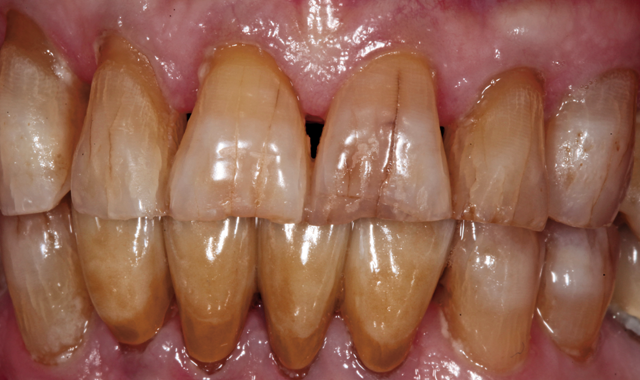

An 88-year-old man presented for restoration of tooth #25, which was fractured and had been endodontically treated (Fig. 1). A thorough intraoral and radiographic examination was performed, which revealed damage to the remaining anterior mandibular teeth incurred over the years as a result of scaling and curettage (Fig. 2). This damage to the

Fig. 2

root surface of the lower incisors-which was visible on the radiograph (Fig. 3)-is known as “Riffle-ization.” Described by Dr. Riffle as a technique for removing every last bit of calculus during repeated root scaling, what is now known as “Riffle-izing," ultimately-over the years-changes the shape of the neck of the tooth to resemble an hour glass.

Therefore, based on the clinical and visual evaluation, the preferred treatment would be to restore the fractured #25 with a post and crown and four splinted crowns to restore the anatomy of the four incisors and increase their resistance to both mobility and fracture.